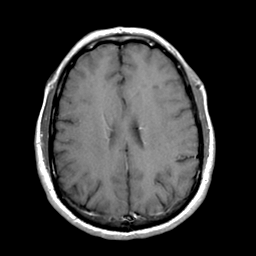

Lyme Encephalopathy:gado enhanced MR -- Slice #20

[Home][Help][Clinical] Slice 20